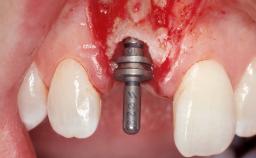

Late Placement of an Implant in a Maxillary Left Central Incisor Site

A 36-year-old female patient was referred for the replacement of the upper left central incisor (tooth 21), which had fractured. Although the tooth had been asymptomatic for many years, the crown began to loosen, at which time she presented to her dentist for an assessment. Teeth 21 and 22 had both been endodontically treated many years previously. She was a healthy individual and a non-smoker.

# of Implants 1

Type of Implants Two-Piece

Attachment Two-Piece

Placement Protocol Early or late implant placement

Loading Protocol Conventional or early